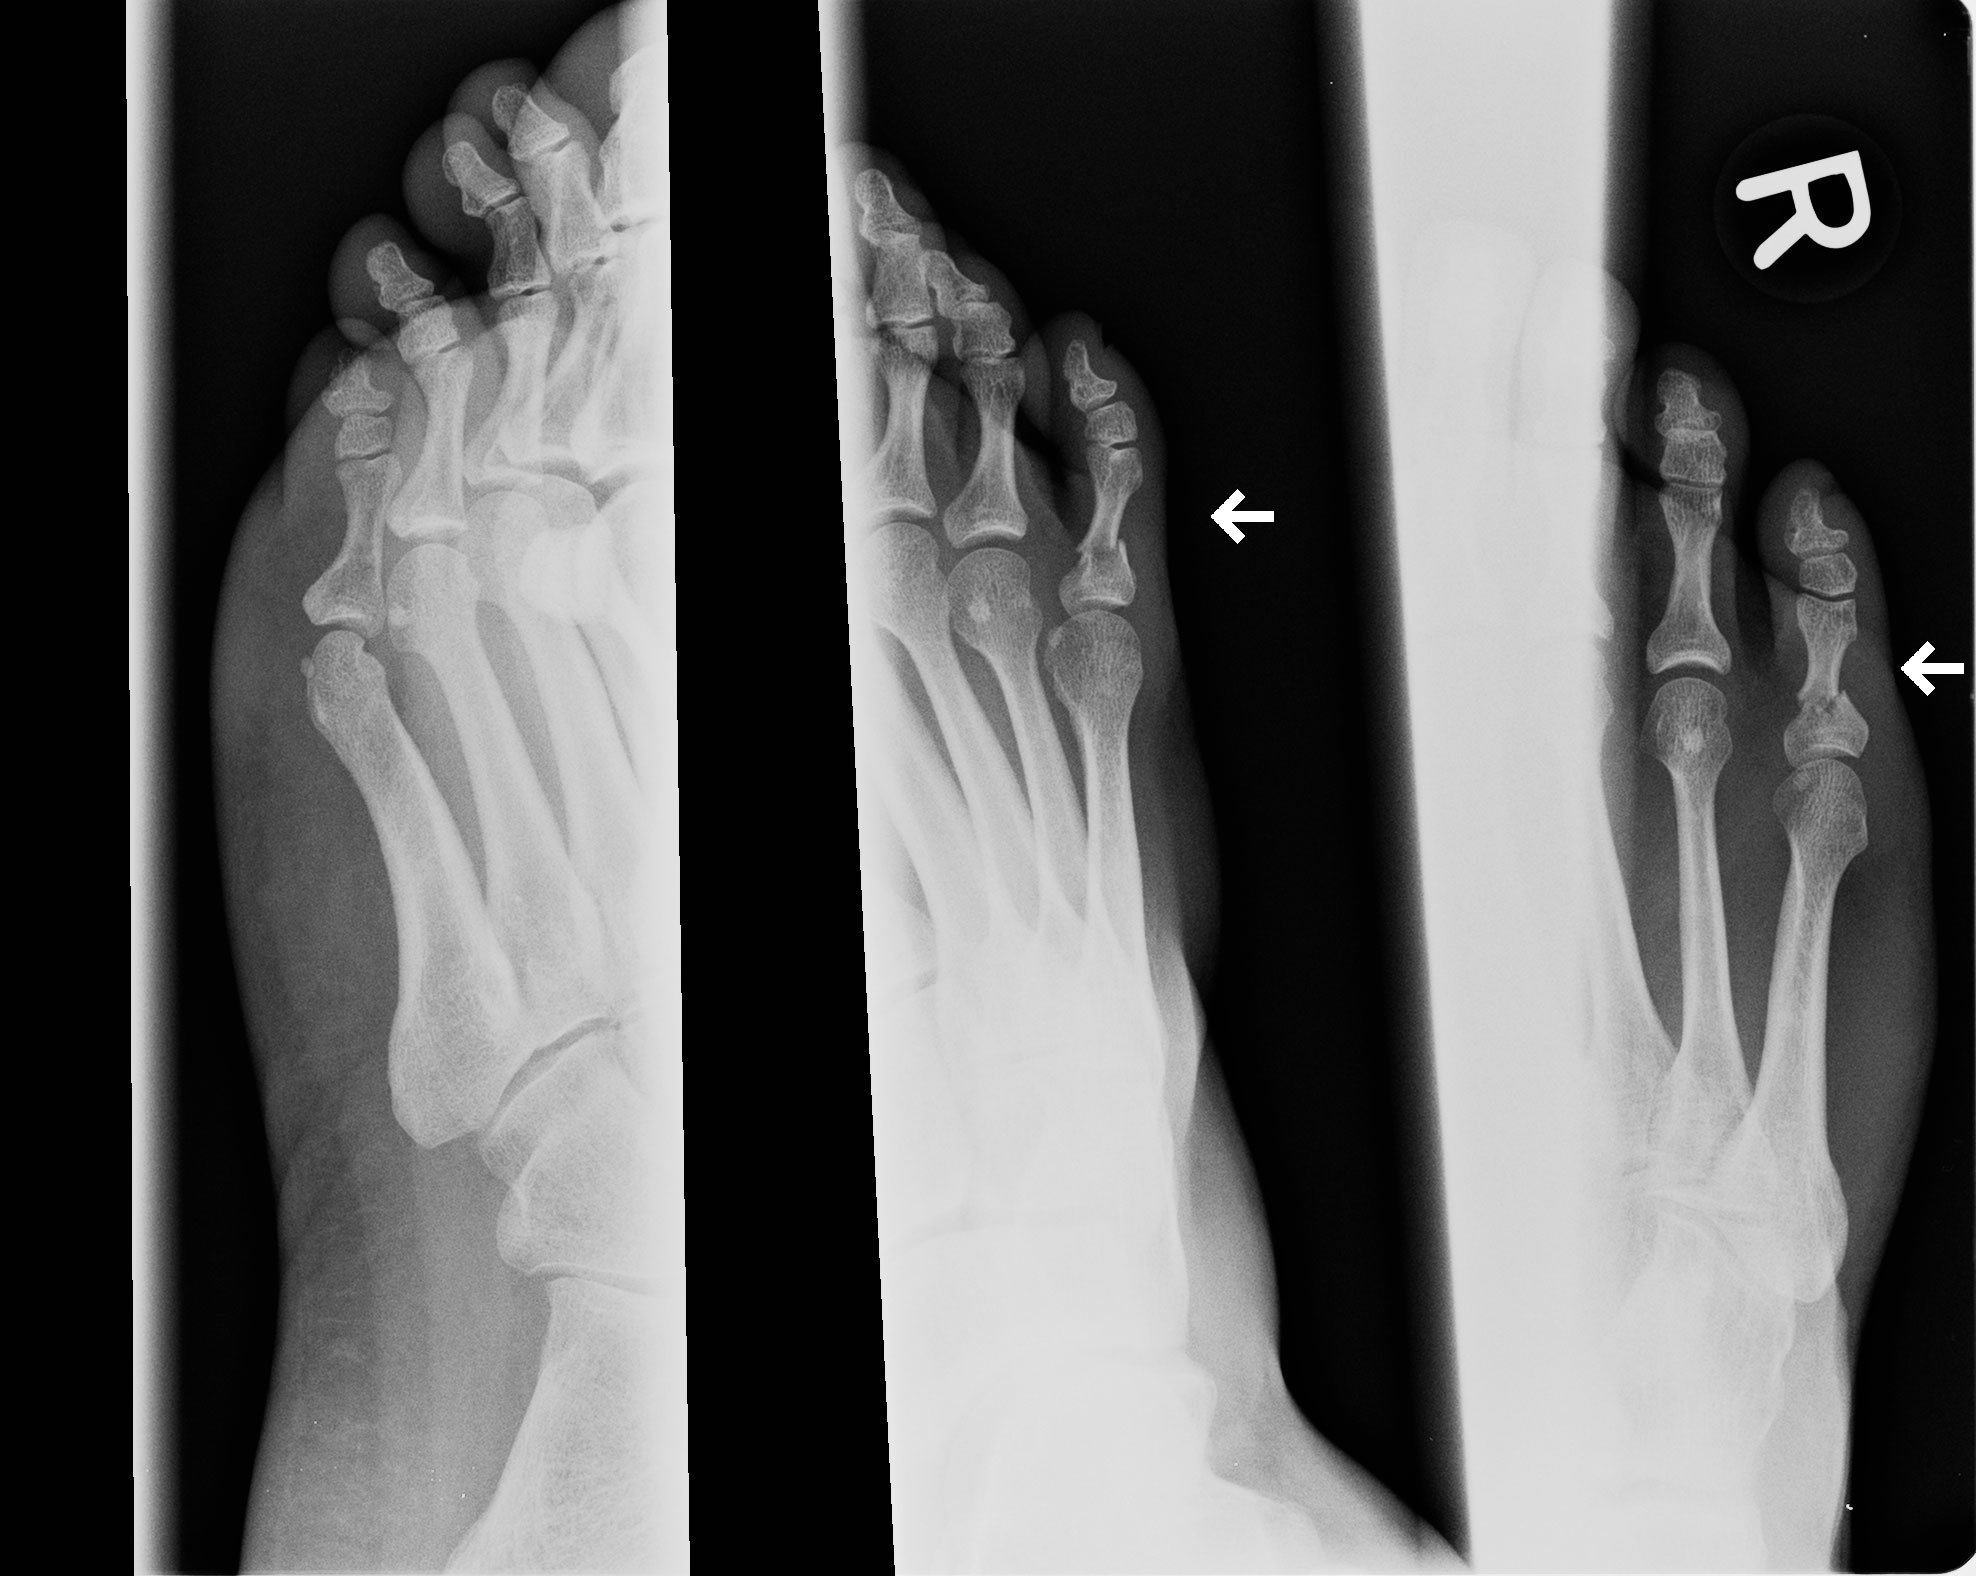

Woytek has suffered a broken toe and will not be able to compete at the tournament and it is to the organisers to decide which fighter will be replacement for Woytek.